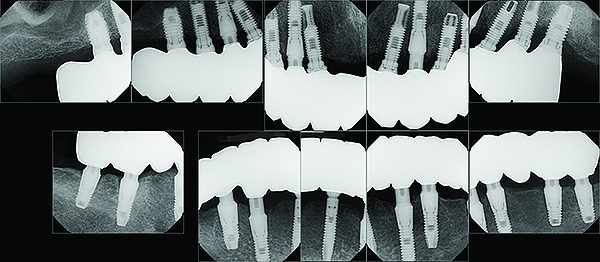

After initial consultation, the preoperative full-mouth radiographs were obtained from the referring periodontist (Figure 1). To address the immediate concern of the patient, replacement of the original crown on tooth No. 11 was provisionally secured to the supporting root. Diagnostic study casts were made of the existing clinical conditions (Figure 2). A complete dental and medical assessment and identification and explanation of treatment objectives was performed. The patient was referred back to the periodontist for confirmation of the implant and periodontal treatment proposals. This included a cone-beam computed tomography (CBCT) scan of the mandible (Figure 3) to aid in optimal implant placement.8 This was then coordinated with the development of the prosthetic sequencing and design. After presentation of the completed treatment plan to the patient, informed consent was obtained.

Fig 1. Pre-treatment full-mouth radiographs.

Figure 1